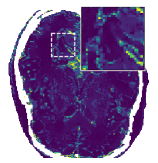

Further PD3O- reconstructions with their corresponding estimated parameter-maps are shown in Figure 14. Note that the parameter-maps are given in a logarithmic scale. As expected, the regularization is strong in constant areas and less strong on edges or finer details in order to reduce a smoothing in these regions.

In Figure 12 we compare the PD3O reconstructions (top) and their corresponding errors with respect to the ground truth (bottom) using different regularization parameter choices , and for PD3O. Obviously, using the estimated parameter-map leads to a significant improvement of the reconstruction. In particular, sharp edges are retained, while using a constant regularizing parameter results in a significant blur. This can be also seen in Table 4, where we compare the NRMSE, PSNR, SSIM and blur and evaluated on the first 100 test images of the LoDoBaP dataset. These results are visualized in Figure 13 using box-plots. Note that the FBP seems to better than PD3O- in terms of the blur effect, but this can be explained by the fact that FBP reconstructions admit a lot of high-frequency artefacts leading to a small blur effect.